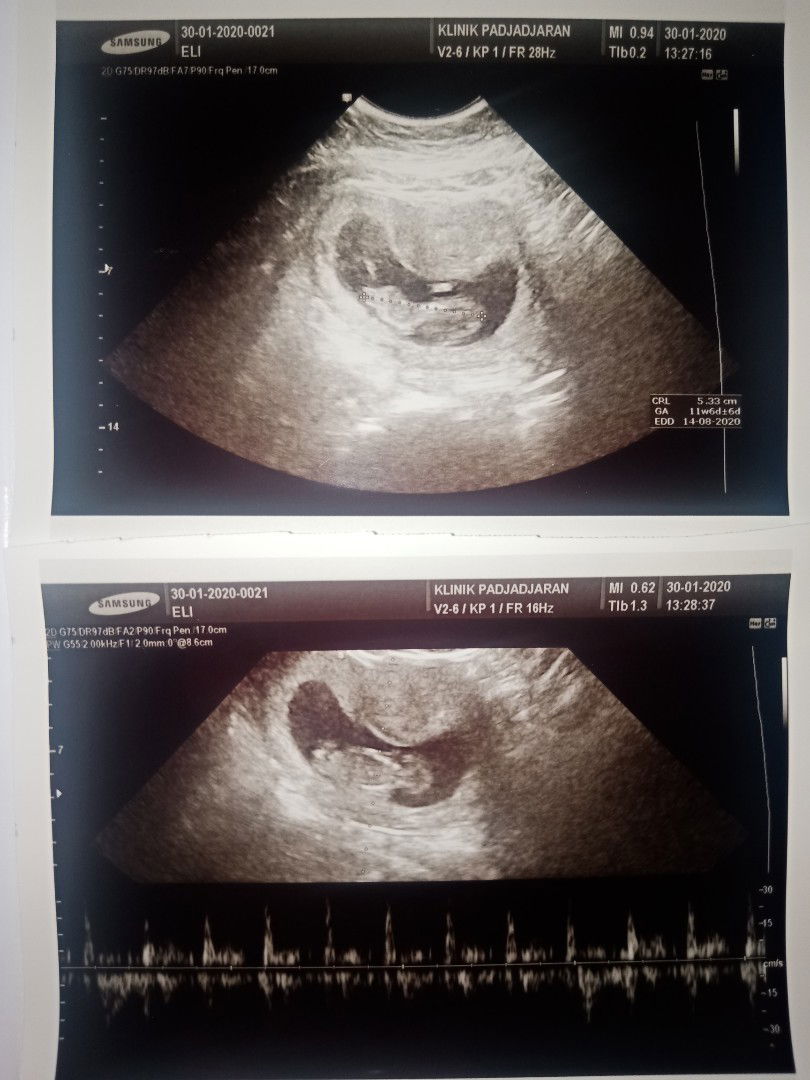

Hasil usg selama 4 bulan 6x USG

Sekedar cerita aja ya bun, Alhamdulillah bun aku seseneng itu lihat perkembangan kehamilan pertama ini , udah 6x USG penuh dengan cerita suka dan dukanya. tiap usg membuat aku senyum2 sendiri,terharu masyaallah ada dedeknya d dalem perutku ? 1.Usg pertama 11Desember2019,aku putusin usg karna udah telat haid slma seminggu dan bnyak perubahan dlm tubuhku dri mualmuntah,sakit payudara. pas usg baru penebalan dinding rahim ,belum terlihat kantung apalagi janinnya. Usg pertama ada kecewanya, sedih dokter belum bisa mastiin aku hamil dan di suruh 2 minggu lgi untuk usg ulang . kta dokternya klo liat dri hsil tespek 70% kemungkinan hamil. 2. Aku usg ulang tgl 07 Januari 2020, setelah menunggu 4 minggu belum haid juga dan mual muntahku smkin mningkat. aku putusin usg lagi mskipun sempet hawatir takut kecewa lgi sama hasilnya. Dan alhamdulillah udah keliatan kantung dan janinnya. 3. usg k 3xnya,20 januari 2020 aku HB sama suami (maap) pdahal baru di mulai bbrpa detik aku lap pke tisu ada cairan coklat gitu . dan kita ga lanjutin, aku berbaring bbrpa jam terus pas aku pipis liat cd ku ada flek coklat . aku baringin lagi aku merasa ga enak perut dan membuat aku semakin waswas aku panik sampe nangis ga karuan . Saat itu lg hujan aku putusin ke bidan terdekat , bidan bilang bismillah aja smoga gpp . aku kurang puas dengan jawaban bidan takut kenapa2 , pulang dri bidan ku liat cd ada flek darahnya aku semakin ga karuan . aku nangis terus2an bun saking paniknya . kemudian hari mulai malam nyari2 dokter spog yg msih buka , walaupun kita harus ngantri lama karna dadakan . sambil nunggu ,nangis terus2an aku sampe pusing tensi tinggi kmudian aku d bwa ruang igd sambil nunggu dokternya . Setelah nunggu alhamdulillah ternyata kata dokter janinnya gpp, baik2 aja . mungkin darah itu karna ada luka di dlm ,tapi bukan dri kandunganku . dokter nyuruh puasa dulu sama suami . 4.usg k 4x tgl 30 januari 2020 , setelah 10 hari aku bedrest fleknya blum hilang juga pdahal udh d ksih penguat kandungan sama dokter, udah bedrest ,dan puasa juga sama suami aku msih panik takut janinnya knpa2 . aku putusin ke spog lagi . beda dokter lagi tapi jawabannya msih sama dede nya baik2 aja , butuh full bedrest aja . dokter bilang flek memang gejala awal keguguran ,apalagi keluar darah selama hamil aplgi usia khamilan yg msih muda itu ga boleh . dokter bilang lihat 2minggu kedepan klo usia nya sudah diatas 13 minggu mulai kuat,jdi di sarankan untuk full bedrest,minum pnguat kandungan dri dokter,dan puasa hb sama suami. 5.usg k 5x nya tgl 13Februari2020, setelah 2 minggu usg ,alhamdulillah selama itu pula aku bedrest aku ga ngalamin lagi flek . Dokter bilang semuanya baik2 aja , dan usg k 5 ini ada yg beda biasanya usg 2D aja dan usg saat itu usg 2D + 3D/4D jd hasil poto usg nya 2 . hasil usg nya usia khmilan saat itu 13w2d . dokter nyuruh usg slnjutnya dijadwalin bulan depan ,sebulan lagi kalo memang gaada keluhan apapun. 6. 12 Maret 2020, nungguin sebulan berasa lama gasabar pengen liat perkembangan dede nya karna aku belum ngerasain kedutan apapun di perutku pdahal UK sudah 17week? . hasil usg nya alhamdulillah prkembangan dede nya semakin bagus , tapi UK setara dengan 18-19 minggu . seminggu lebih tua karna bbj nya 240gr ,tapi dilihat dri apk UK 17 mnggu itu harusnya 110-140gr . aku sempet khawatir juga tapi dokternya bilang normal2 aja . oh iya seperti bulan sblmnya usg k 6x juga 2D+3D/4D lagi , dan poto usg yg 2D nya kali ini hanya kepala sama perut . tapi dokternya udah jelasin semuanya sewaktu usg . nah gitu bun ceritaku selama 4 bulan ini, alhamdulillah dinikmatin setiap prosesnya bersyukur banget bisa smpe di titik ini . 7.poto ke 7 itu acara tasyakur 4 blanan kemaren , alhamdulillah semua berjalan lancar . aku berharap kita semua, bunda2 dan dedeknya sehat2 hingga lahiran tiba ??.terimakasih untuk yg bersedia baca cerita kehamilanku ini ❤️?